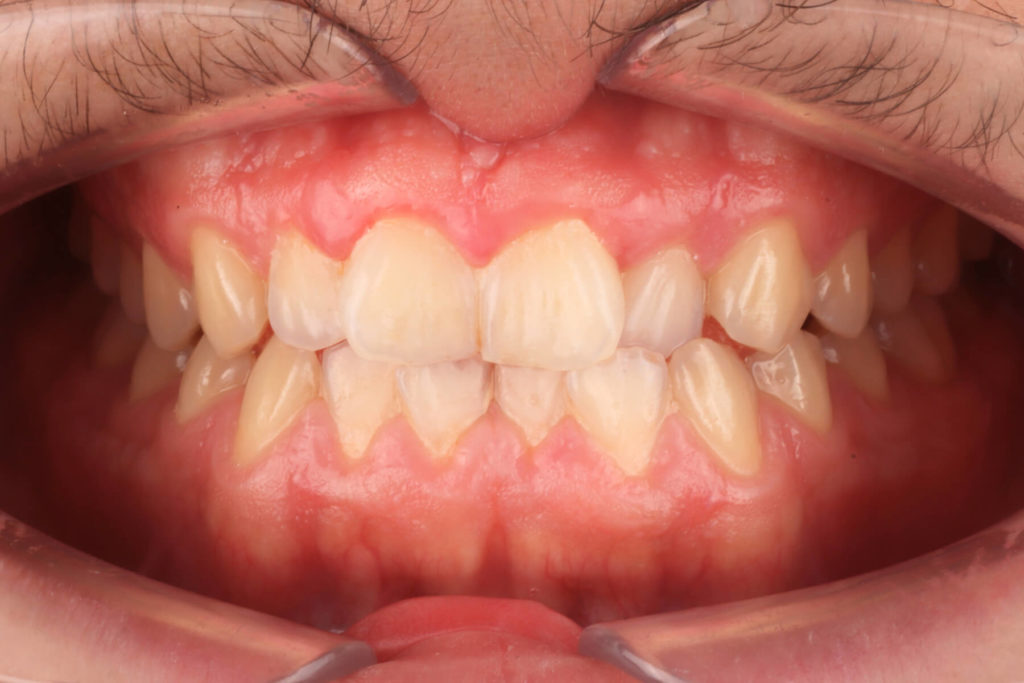

SITUACIÓN INICIAL

CLASE I MORDIDA CRUZADA EN LATERALES

• Clase I con mordida cruzada en los incisivos laterales.

• Apiñamiento moderado en el arco superior e inferior.

• Desplazamiento de la línea media superior.

• Arco normal con necesidad de expansión.